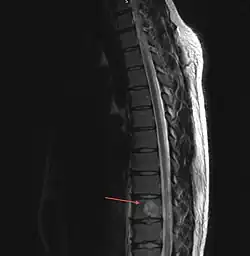

Hämangiome der Wirbelsäule

Ein vertebrales Hämangiom ist der häufigste gutartige Tumor der Wirbelsäule und betrifft bis zu 10 % der Gesamtbevölkerung. Er wird meist zufällig bei Untersuchung der Brustwirbelsäule durch bildgebende Verfahren wie CT oder MRT entdeckt und ist dort besonders häufig zwischen den Wirbeln T3 bis T9 zu finden. Normalerweise symptomfrei, bedarf er im Allgemeinen keiner Behandlung. Die häufigste Form und Größe entspricht in etwa der Abgebildeten; kann jedoch auch den gesamten Wirbelkörper umfassen.